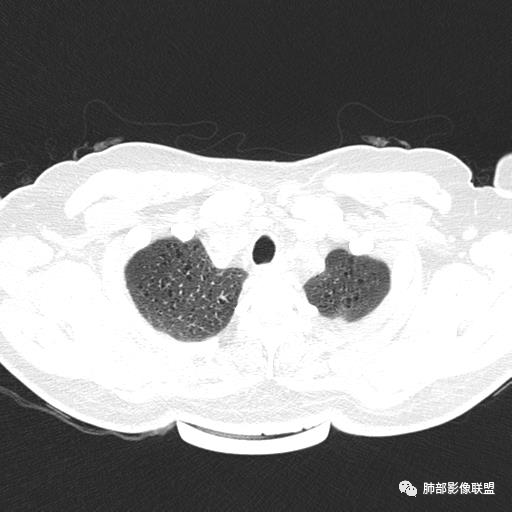

中年女性,不吸烟

双肺弥漫囊腔,累及肋膈角,囊腔形态相对规则单一。

符合LAM